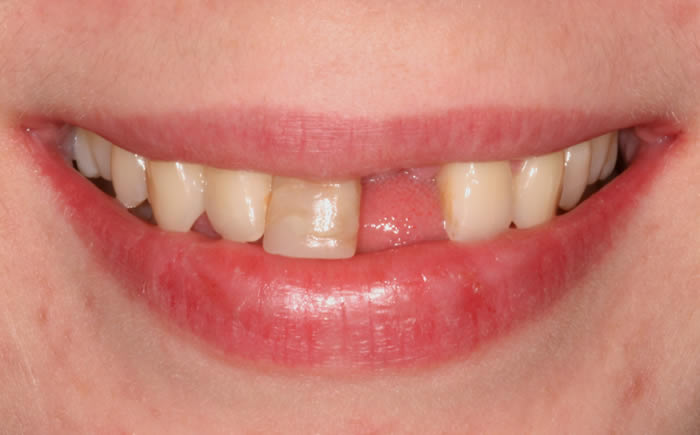

Missing upper front tooth replaced by dental implant and crown